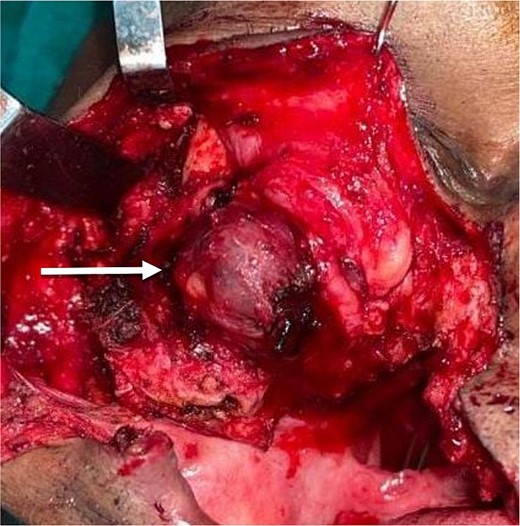

The planned treatment was local excision under general anesthesia. For resection of the tumor, a Weber–Fergusson incision was taken from the pre-existing surgical scar over the right side. The tumor mass was resected along with the lateral wall of the orbit of the right side, the floor of the orbit, and the right zygomatic arch, shown in Fig. 2. Standard marking for the hemicoronal incision over the right side was done for harvesting the temporalis myofascial flap. The flap was tunneled under the floor of the orbit and sutured over soft tissue on the medial wall of the orbit. Closure was done after securing a minivac drain.